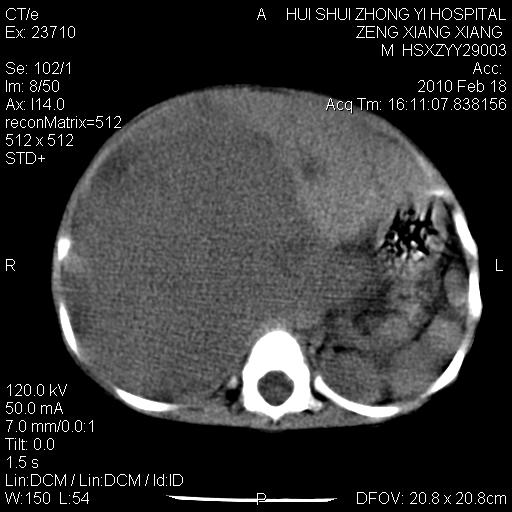

标题: PED3106:男,2岁,腹胀1月。 [打印本页]

标题: PED3106:男,2岁,腹胀1月。

考虑肝母细胞瘤

肝母细胞瘤可能性大,右肾形态大体可见,不支持肾母细胞瘤,右肾移位不明显,肾上腺神经母细胞瘤可能性不大。